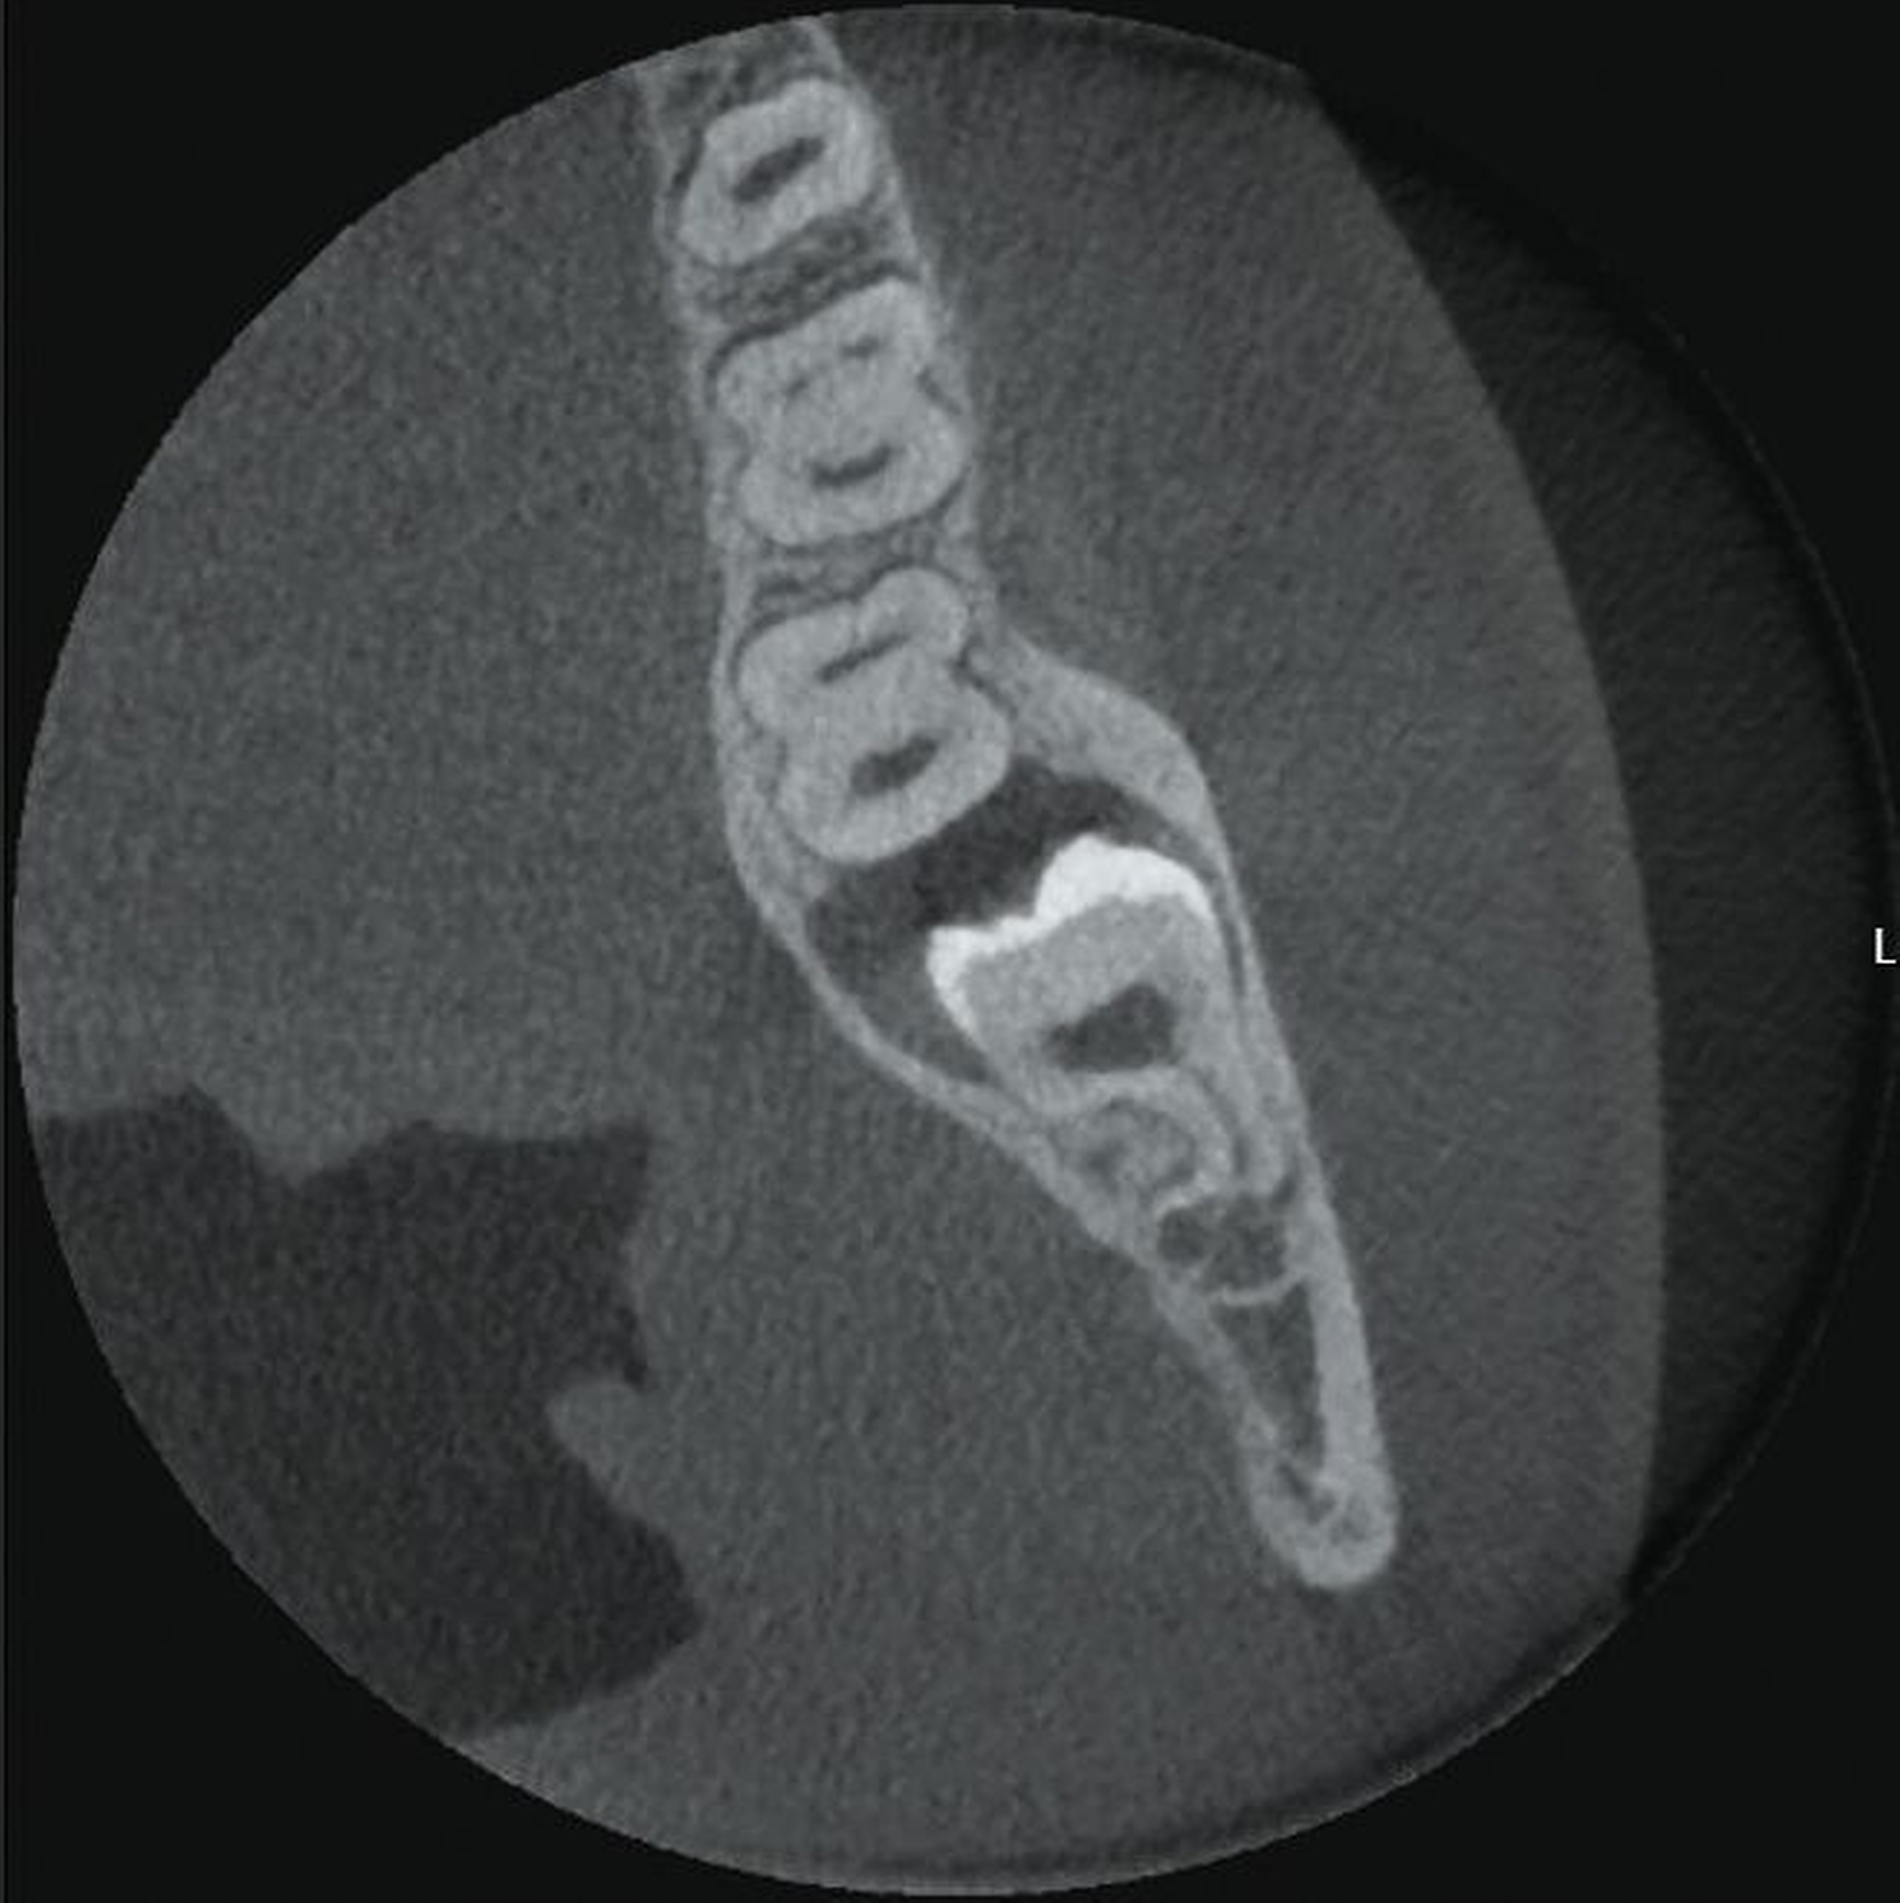

Im Unterkiefer linksseitig zeigt sich der Canalis mandibularis lingual verlaufend, in enger Lagebeziehung zur Wurzel des retinierten und ebenfalls nach mesial gekippten Zahnes 38 (Abbildung 3).